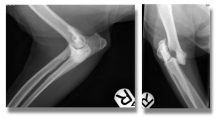

Treatment of concurrent Cranial Cruciate Ligament Rupture and Medial Patellar Luxation

Treatment of concurrent Cranial Cruciate Ligament Rupture and Medial Patellar Luxation with a modified Tibial Plateau Levelling Osteotomy and ...